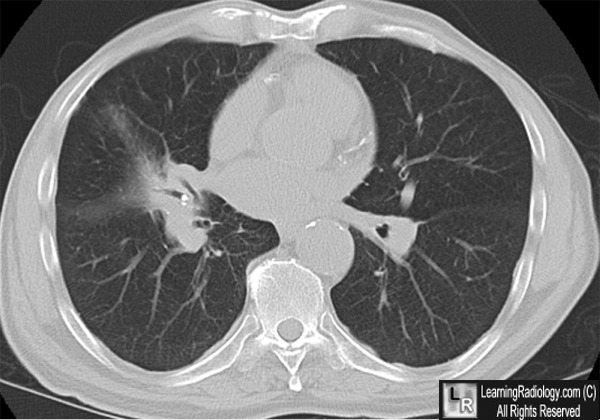

Фотографии заболеваний бронхолегочной системы